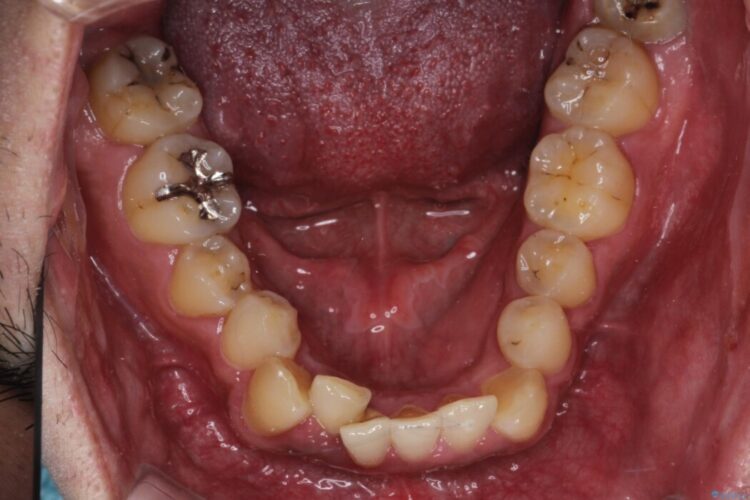

反対になっている嚙み合わせを改善したいとご来院されました。

診査の結果、上下左右4番の歯を抜歯し、審美装置にて反対咬合と叢生を改善していくこととしました。

骨格性Ⅲ級を示しましたが、構成咬合位がとれたことから反対咬合と叢生改善のため、上下左右第一小臼歯を抜歯しワイヤー矯正を行いました。途中、バイトアップを行っています。